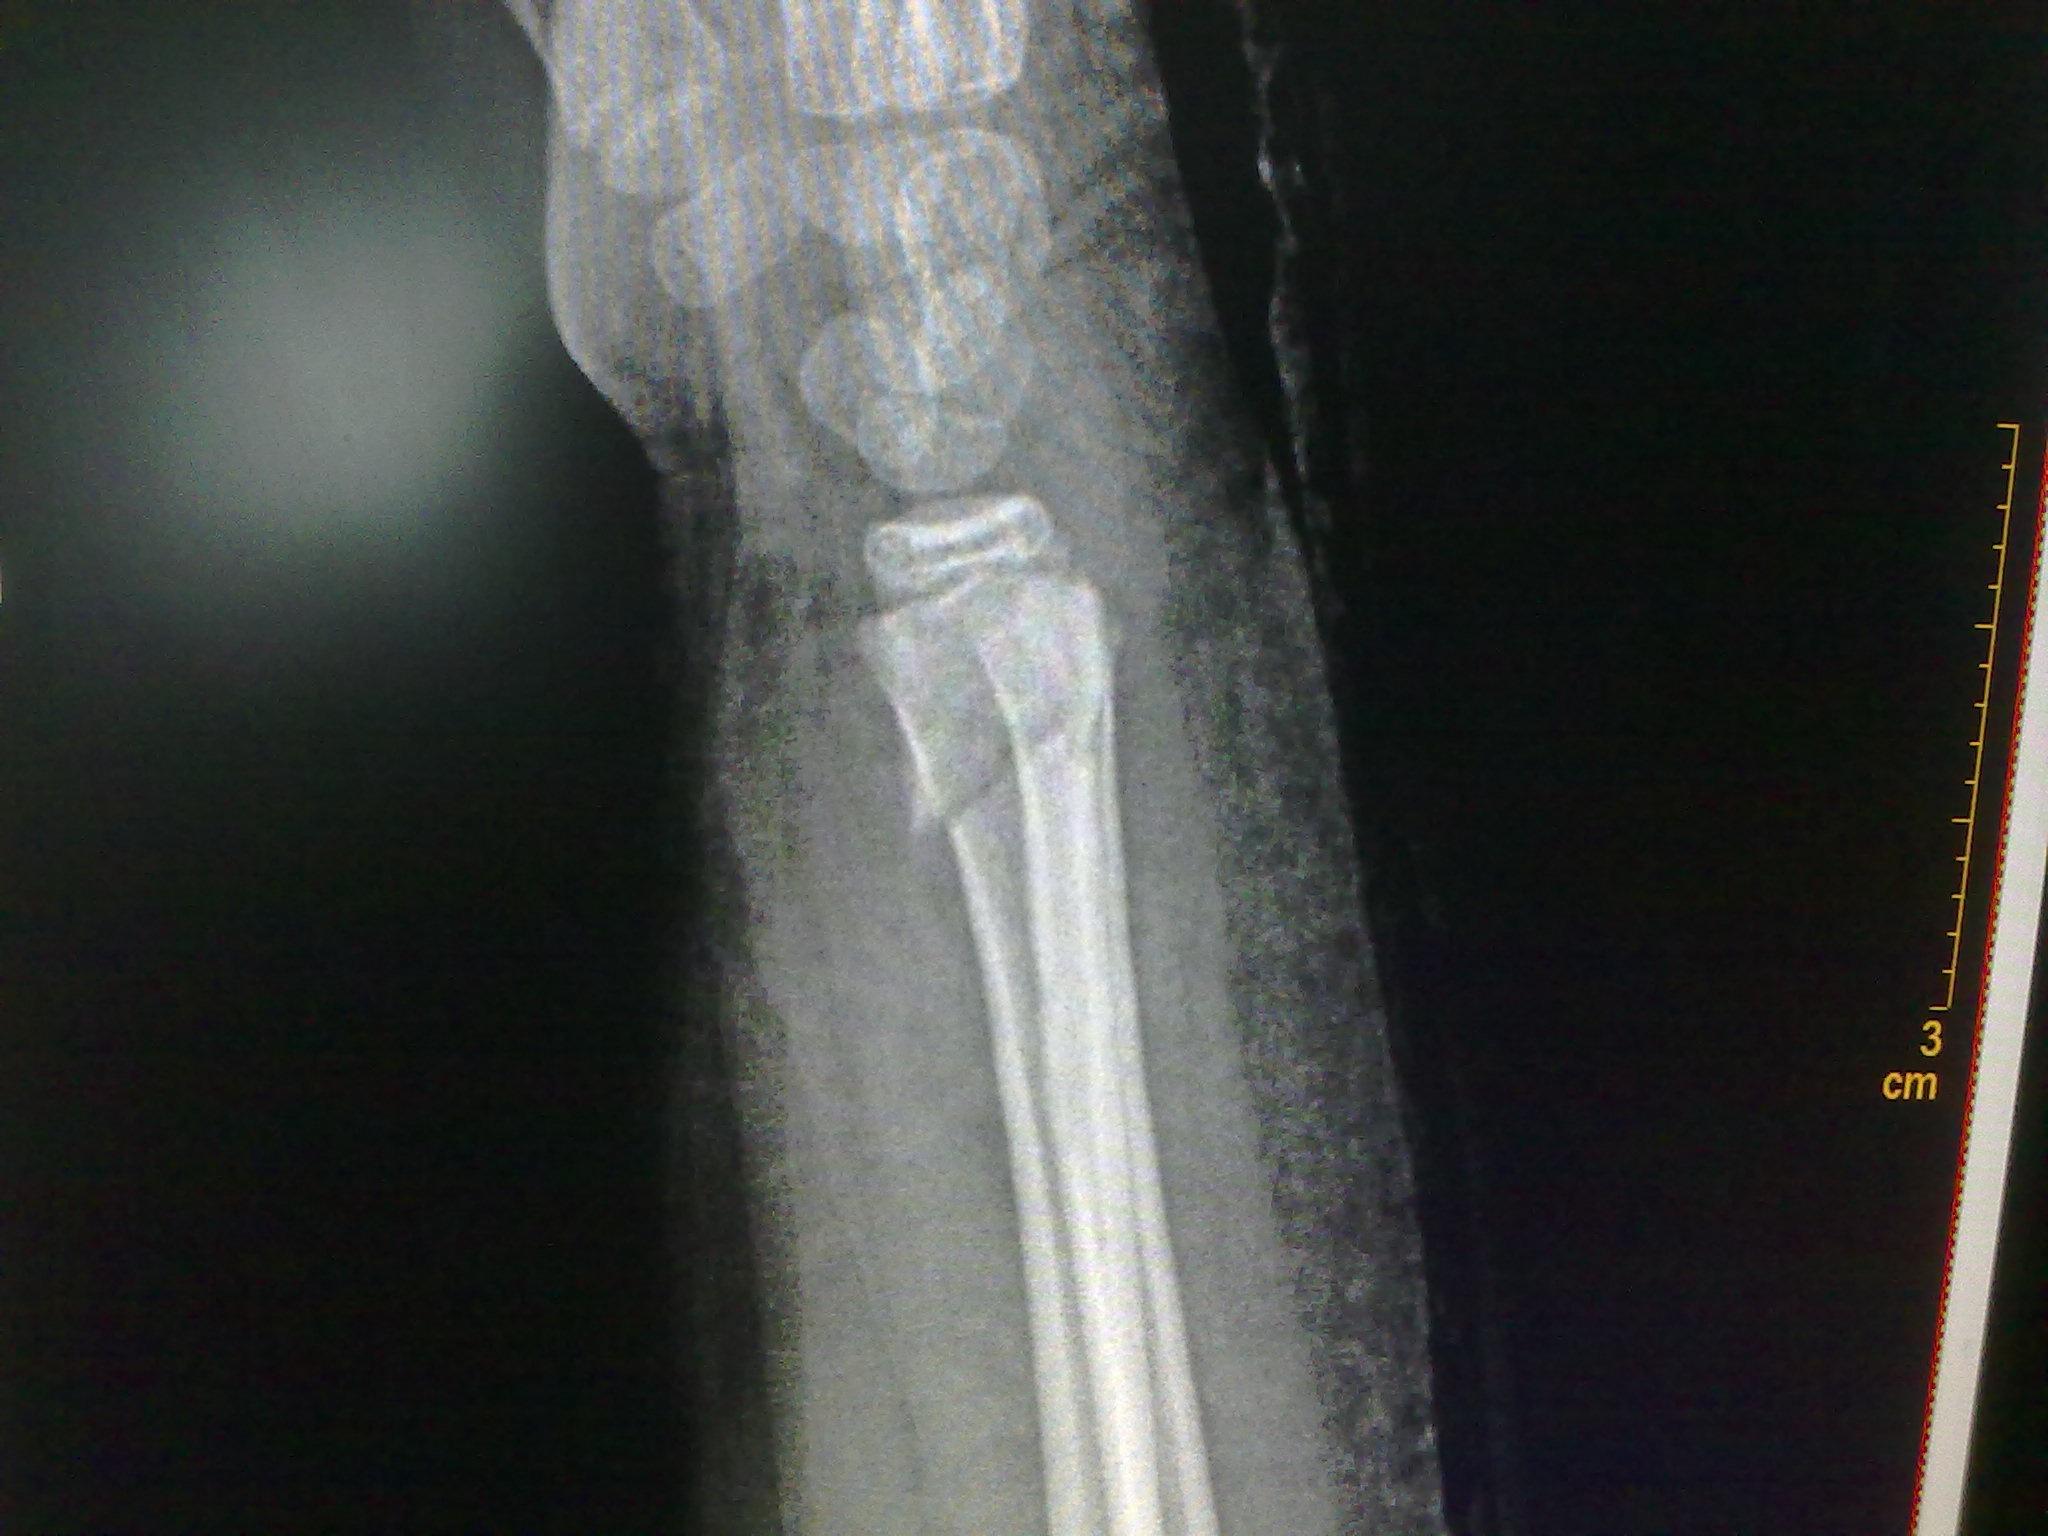

colles骨折手法整复需要麻醉吗整复后患者极度不适

图片尺寸2430x3370